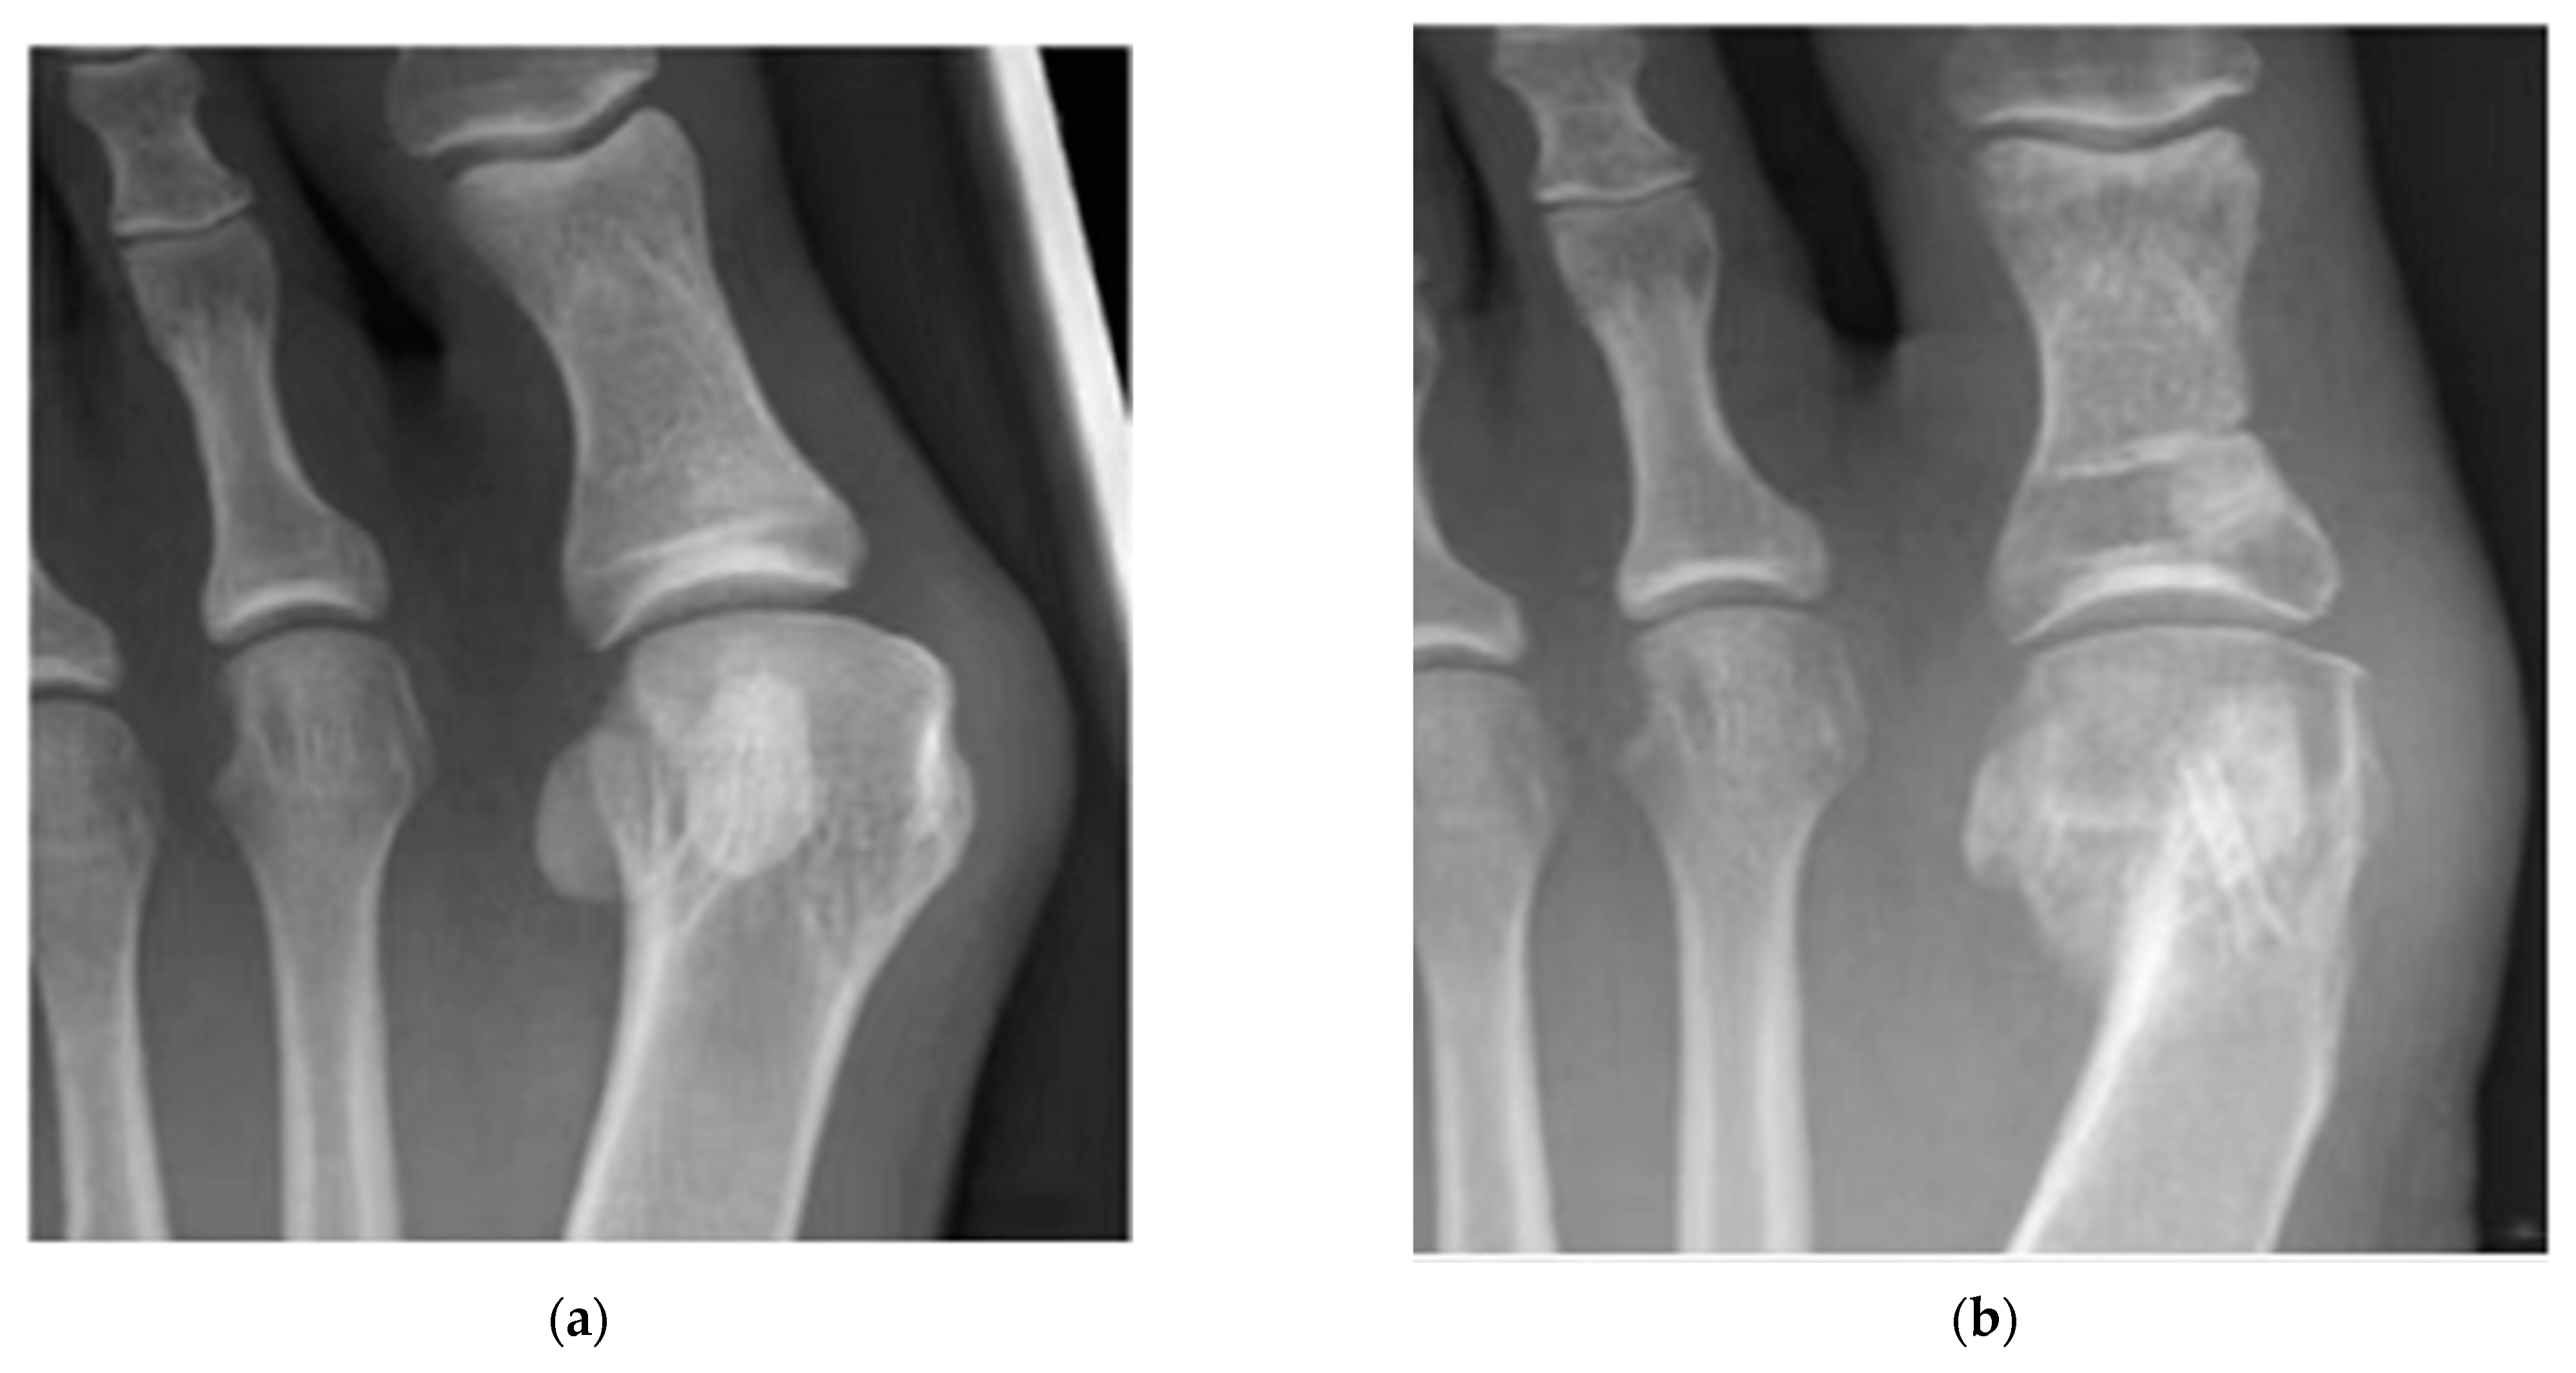

- Plaass, C.; von Falck, C.; Ettinger, S.; Sonnow, L.; Calderone, F.; Weizbauer, A.; Reifenrath, J.; Claassen, L.; Waizy, H.; Daniilidis, K.; et al. Bioabsorbable Magnesium versus Standard Titanium Compression Screws for Fixation of Distal Metatarsal Osteotomies—3 Year Results of a Randomized Clinical Trial. J. Orthop. Sci. 2018, 23, 321–327. [Google Scholar] [CrossRef]

| Mg-Y-RE-Zr screws | Bunion correction | 13 | Germany | All healed | [202] |

| Mg-Y-RE-Zr screws | Bunion orthopaedics | 40 | Germany | 79% healing after 6 weeks, 90% healing after 12 weeks | [202] |

| Mg-Y-RE-Zr screws | Bunion orthopaedics | 100 | Germany | All healed | [202] |